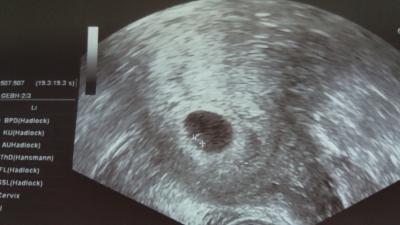

Ein hämatom erkennen Lg

Bild zu Kann hier jemand - Schwanger - wer noch? Rund um die Schwangerschaft

Zufällig ja hatte auch eins... Deines sieht gigantisch aus ähnlich wie meins war...gefährden die Frucht mit abzureißen...bei mir kam das Hämatom von nem Zwilling der abging..hab 4 Monate geblieben. ...sry das der Text so brutal klingt ist sonst so viel text...PS .. mein sohn kam zwar ohne Zwilling aber gesund auf die Welt und macht nun schon fast 3 Monate fleißig die pempers voll :)

Lass Dir keine Angst machen !!! Nein, ich sehe da nur eine Gebärmutter mit einer Früh-SS - sonst gar nichts! LG Pearl

... ich denke, man muss immer damit rechnen, wenn man sowas in einem Forum zur Diskussion stellt, aber : ich finde, so etwas sollte man nur beurteilen, wenn man auch Ultraschall-Erfahrung hat, alles andere macht einfach nur Angst. LG